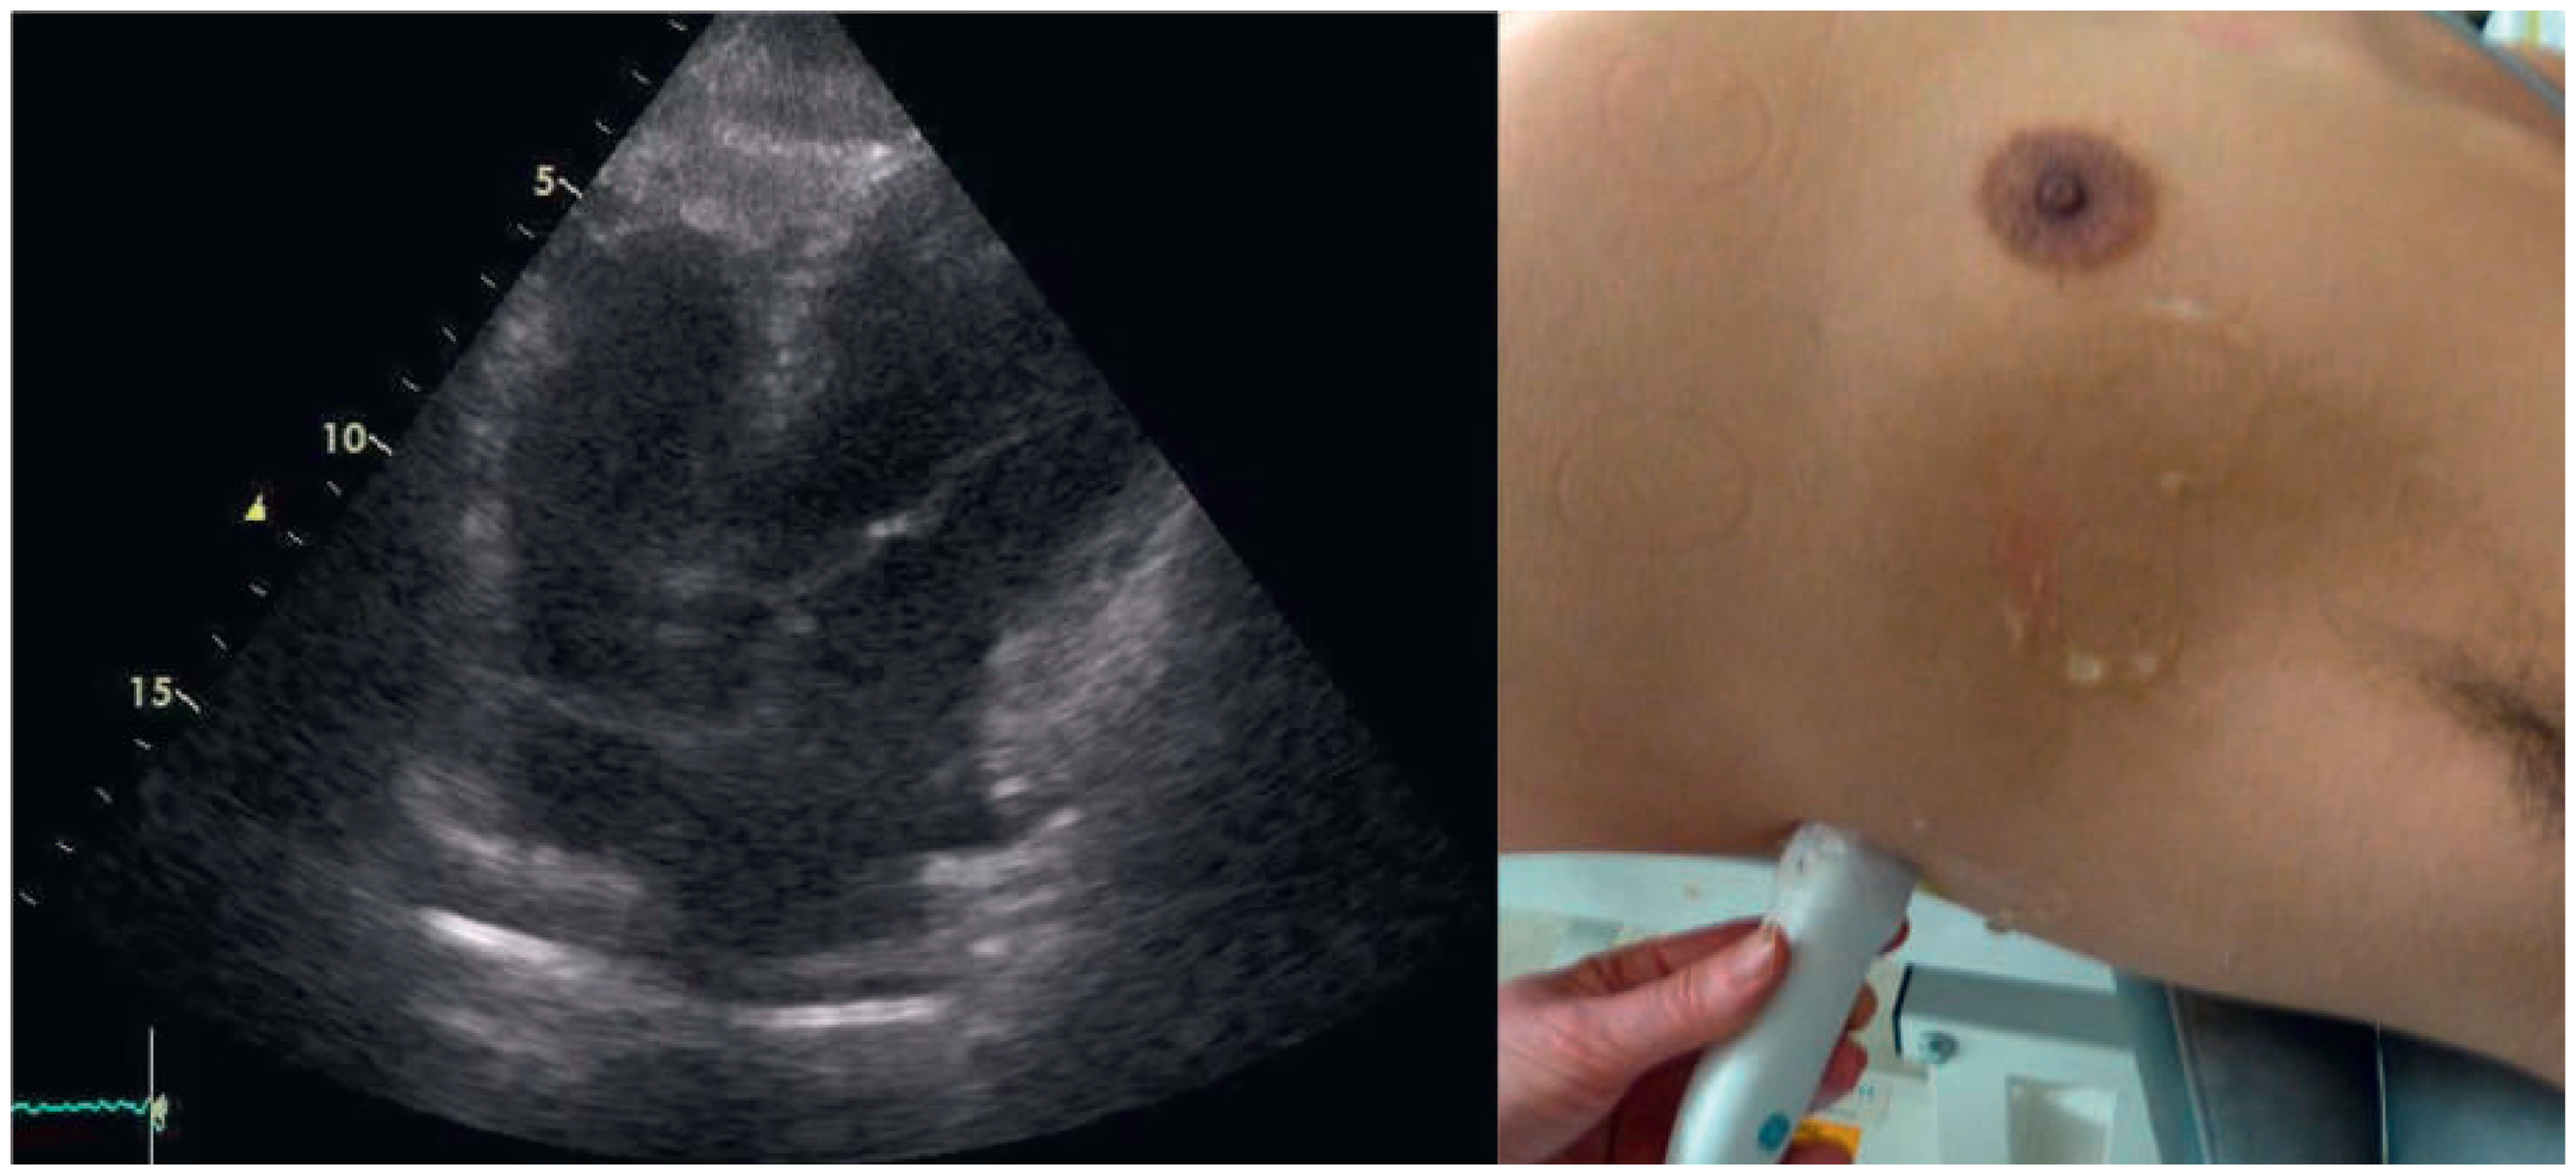

A 57-year-old male presented to the medical outpatient department with typical angina pectoris Canadian Cardiovascular Society (CCS) class II and dyspnoea on exertion during the previous weeks. Additionally he had retrosternal pain at rest and dyspnoea during the previous night. The patient had a a history of untreated arterial hypertension. On initial workup, the patient was in a stable cardiovascular condition with an office blood pressure of 150/88 mm Hg, and the cardiac examination was unremarkable. Blood tests revealed serially negative high-sensitivity troponins. Glycated haemoglobin was 6.4%, consistent with prediabetes, and lowdensity lipoprotein cholesterol was 2.5 mmol/l. An electrocardiogram (ECG) showed sinus rhythm, right axis deviation, signs of an incomplete right bundle-branch block with rR’ morphology in leads V1 to V4, and lateral displacement of the transition zone in the precordial leads, but no signs of acute ischaemia (Figure 1). On echocardiography, the image acquisition was difficult with a typical long axis view acquired in the fifth intercostal space in the midaxillary line (Figure 2) and apical views acquired from a posterolateral window (Figure 3). Computed tomography angiography (CTA) of the heart showed that the entire heart was displaced leftwards into the left hemithorax. Also evident was a lingula of lung tissue interposed between the aorta and the pulmonary artery indicating a congenitally absent pericardium (Figure 4). Additionally, the CT scan revealed coronary artery disease with soft plaques and >70% stenoses of the left anterior descending artery (LAD), the left circumflex artery (50%–70% stenosis) and the first marginal branch (>70% stenosis). Considering the diagnosis of a congenitally absent pericardium, the ECG was repeated, with leads V7–V9, showing a normal R-progression from V4 to V9 (Figure 5). Coronary angiography with primary stenting of a 95%–99% stenosis of the LAD artery and a 75%–95% stenosis of the first marginal branch resulted in complete resolution of symptoms.

Figure 2. Transthoracic echocardiography. Long axis view of the left ventricle acquired in a left lateral window.

Congenitally absent pericardium is a rare condition found in 1/10 000 autopsies with morphological patterns of: total bilateral absence (extremely rare); partial left absence (70%); and partial right absence (17%) [1]. It may be associated with other congenital defects such as atrial septal defects, persistant ductus arteriosus, bicuspid aortic valve or tetralogy of Fallot [2]. Most patients are asymptomatic but absent pericardium may cause paroxysmal, stabbing, nonexertional chest pain. In partial left absence severe complications may be caused by herniation of parts of the heart resulting in shortness of breath, syncope or sudden death [1,2]. On ECG, partial right bundle-branch block is common and displacement of the transition zone in the precordial leads is seen as a result of the displacement of the heart [2]. On transthoracic echocardiography, the standard views are found to be displaced leftwards as is exemplified in Figure 2. The diagnosis is usually established by use of CT or magnetic resonance tomography showing displacement of the heart into the left hemithorax and lung tissue interposed between the aorta and the main pulmonary artery [2]. In symptomatic patients, and especially in patients with risk factors or symptoms of herniation, surgical therapy with pericardioplasty may be performed [1,2]. Our patient was symptom-free after coronary angiography and no treatment due to the congenitally absent pericardium was necessary.